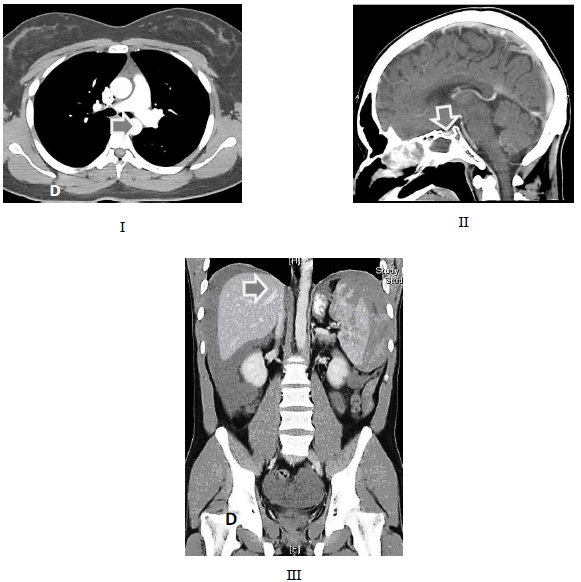

As setas nas figuras acima apontam respectivamente estruturas anatômicas nos exames de tomografia computadorizada. Marque a alternativa que apresenta a sequência correta.